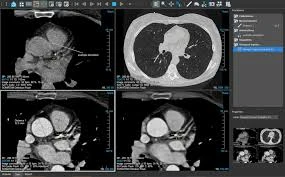

A CT scan viewer is a sophisticated software application designed to display CT images with exceptional clarity and detail. It allows medical professionals to analyze the results and make informed decisions regarding diagnosis and treatment. With advancements in medical imaging technology, CT scan viewers have become more user-friendly, efficient, and feature-rich, making them essential tools for radiologists and healthcare professionals.

Modern CT scan viewers offer advanced features such as 3D rendering and image manipulation. These capabilities allow radiologists to view CT images from multiple angles and in three dimensions. By creating 3D reconstructions of scanned areas, healthcare professionals can gain a better understanding of the size, location, and shape of medical conditions. For instance, in oncology, 3D rendering can help doctors visualize the exact position of tumors, making it easier to plan surgeries or treatment protocols. The ability to manipulate and rotate images in real-time significantly enhances diagnostic accuracy and improves clinical decision-making.

As a leader in the field of medical imaging solutions, Nandico has played a significant role in advancing CT scan viewers and improving diagnostic accuracy. Nandico’s Radiant DICOM Viewer, a state-of-the-art CT scan viewer, provides exceptional image quality, intuitive navigation, and robust diagnostic tools. With its easy-to-use interface, healthcare professionals can quickly analyze and interpret CT images, leading to faster diagnoses and better patient outcomes.

Moreover, Nandico’s software offers advanced features like 3D rendering, image annotation, and measurement tools, all of which enhance the diagnostic process. These capabilities are particularly valuable for oncologists, neurologists, and surgeons who rely on detailed CT images for treatment planning and decision-making.